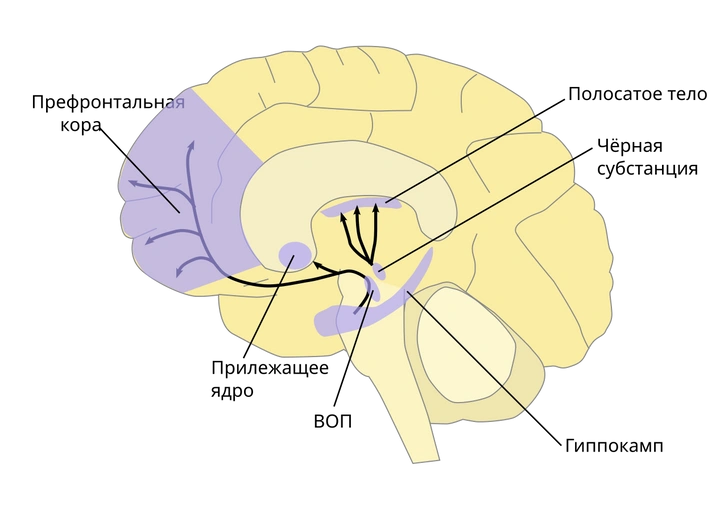

В 2005 году группа американских ученых во главе с антропологом Хелен Фишер мозг 17 влюбленных с помощью функциональной магнитно-резонансной томографии (ФМРТ). Оказалось, что, когда человек смотрит на фото любимого, в его мозге активируются расположенные в правом полушарии части хвостатого ядра (входит в состав полосатого тела) и вентральной области покрышки среднего мозга (ВОП).

Наравне с прилежащим ядром, миндалевидным телом, черной субстанцией, префронтальной корой и гиппокампом эти структуры входят в так называемую систему вознаграждения (положительного подкрепления), которая закрепляет определенное поведение, поощряя человека ощущением удовольствия и другими положительными эмоциями за счет выработки и поступления в определенные области нейромедиатора дофамина, который нередко ошибочно называют «гормоном удовольствия».

Одновременно состояние влюбленности фактически некоторые связи в мозге, отвечающие в том числе за негативные эмоции и критическую оценку других людей. В частности, речь идет о связи между префронтальной корой и прилежащим ядром, а также прилежащим ядром и миндалевидным телом. Поэтому-то любовь и слепа в отношении недостатков объекта влечения — красные флаги не видны сквозь розовые очки.